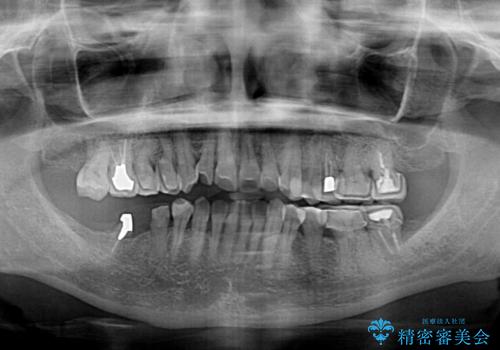

- 治療をおこなって以来、クラウン周りの歯肉から出血が続くとのことで来院された患者様です。

診察を行ったところ、クラウンと歯の境目が不適合で汚れが溜まりやすく、炎症を起こしている状態でした。

治療を終えたばかりですが、出血を改善するためには作り直しが必要と判断し、オールセラミッククラウンにて補綴治療することとしました。

他にも、咬合時に痛みを感じる歯や、欠損により咬みにくい奥歯などをインプラントを用いて治療を行うこととしました。

右下は、残存歯の状態があまり良くなかったため、今後抜歯となったことを想定して、最後臼歯のインプラントを決定しました。